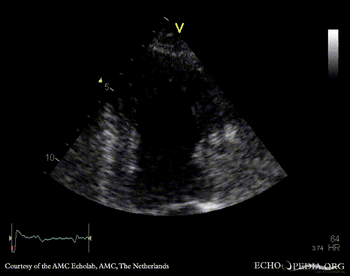

Case 112